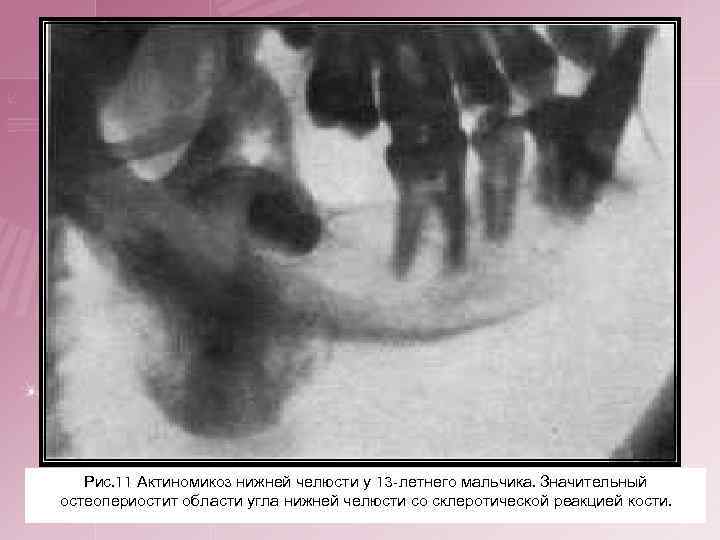

4. Актиномикоз костей и суставов. Эта форма возникает или в результате перехода актиномикозного инфильтрата с соседних органов, или является следствием гематогенного заноса гриба. Описаны поражения костей голени, пяточной кости, таза, позвоночника, нижней челюсти, а также коленного и других суставов. Нередко процессу предшествует травма. При поражениях суставов функция серьезно не нарушается. При образовании свищей возникают характерные изменения кожи.

Рис. 11 Актиномикоз нижней челюсти у 13 -летнего мальчика. Значительный остеопериостит области угла нижней челюсти со склеротической реакцией кости.